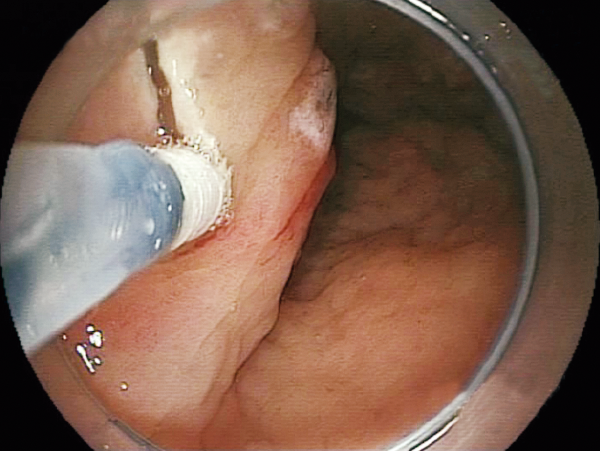

Injection of saline or submucosal injection agent*1 into the submucosal layer which is exposed after dissection can be performed.